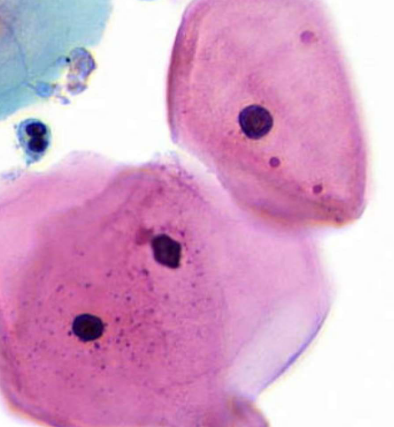

squamous cells

squamous cell carcinoma